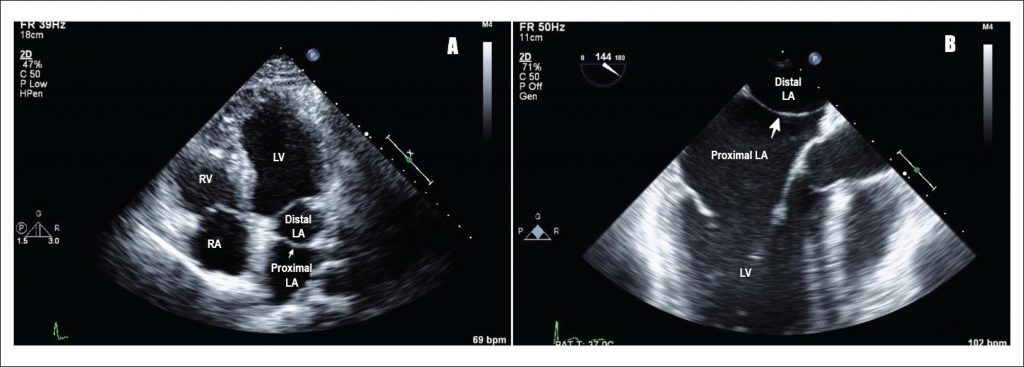

Cor Triatriatum Sinistrum

A 25-year-old male presented to clinic with complaints of palpitations. Transthoracic echocardiogram (TTE) showed presence of a membrane in left atrium suggestive of cor triatriatum []. This finding was confirmed with transesophageal echocardiogram (TEE), which revealed a membrane in the left atrium attaching at the Coumadin ridge and the atrial septum, just caudal to the fossa ovalis [].